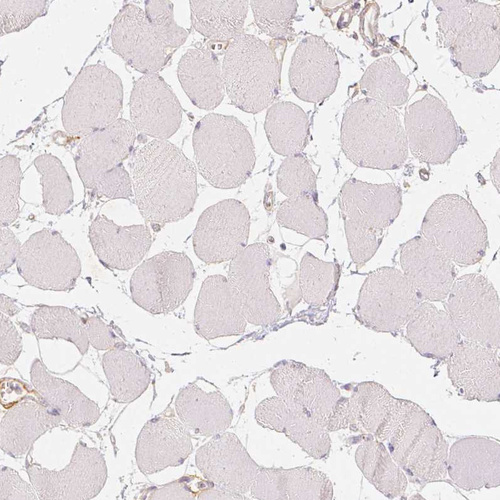

Immunohistochemistry analysis in human cerebral cortex and skeletal muscle tissues using AMAb90846 antibody. Corresponding THY1 RNA-seq data are presented for the same tissues.